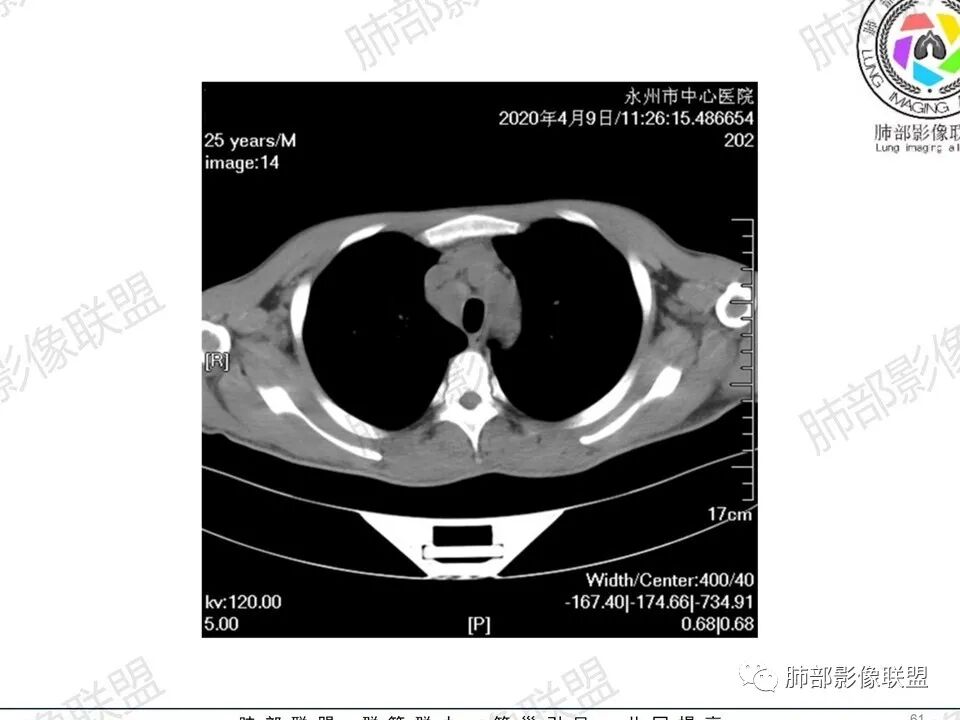

3、影像表现:双肺散在斑片影及结节影,部分结节内可见血管穿行,斑片影沿支气管血管束分布,近胸膜侧病变收缩不明显。部分中央淋巴间质增厚,小叶间隔增厚。病灶内支气管穿行,部分支气管略扩张。局部小结节呈串珠样改变。纵隔、肺门区、锁骨上及腋窝淋淋巴结肿大,部分有融合。心腔低密度。脾大。

5.双肺门及纵隔淋巴结显著增大,这改变相当显眼。这里强调“双肺门”及“多发”!

增大的淋巴结密度偏低且均匀。此外患者有体表淋巴结增大。

6.心腔密度减低。提示可能存在贫血。

1.临床表现明显,纵隔及双肺门淋巴结显著肿大,临床最为担心的还是淋巴瘤!

尤其患者有贫血及脾脏增大,又有体表淋巴结增大时,这也是临床相对常见的情形。